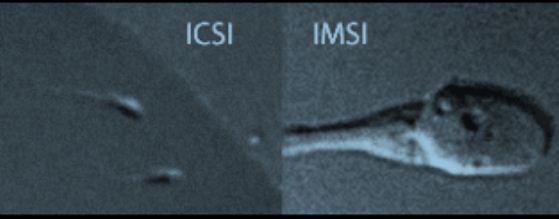

رابع : إختيار الحيوانات المنوية بالتكبير المتناهي Intracytoplasmic Morphologically Selected Sperm Injection (IMSI ) يتم تكبير الحيوان المنوى من خلال الحقم المجهرى العادى حتى 200-400 مرة ولكن بإستخدام هذه التقنية يتم التكبير بأكثر من 6000 مرة بحيث قد تظهر عيرب معينة برأس الحيوان المنوى وقد وجدت الأبحاث أن العيوب التى تظهر تحت هذا التكبير ترتبط بوجود أجنة غير سليمة ولما إستخدمت هذه التقنية إرتفعت نسب الحمل والولادة ويظهر فى الصورة الأتية الفرق بين شكل الحيوان المنوى بالتكبير العادى مقاؤنة بالتكبير المتناهى